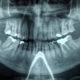

Nuova Dentiera

Vorrei farmi una nuova dentiera completa perché adesso ne ho una vecchia, devo venire nel vostro studio molte volte?

Dovrebbe venire nel nostro studio solamente una volta, entrerebbe nello studio la mattina ed andrebbe via dopo 5-6 ore con una protesi nuova terminata.